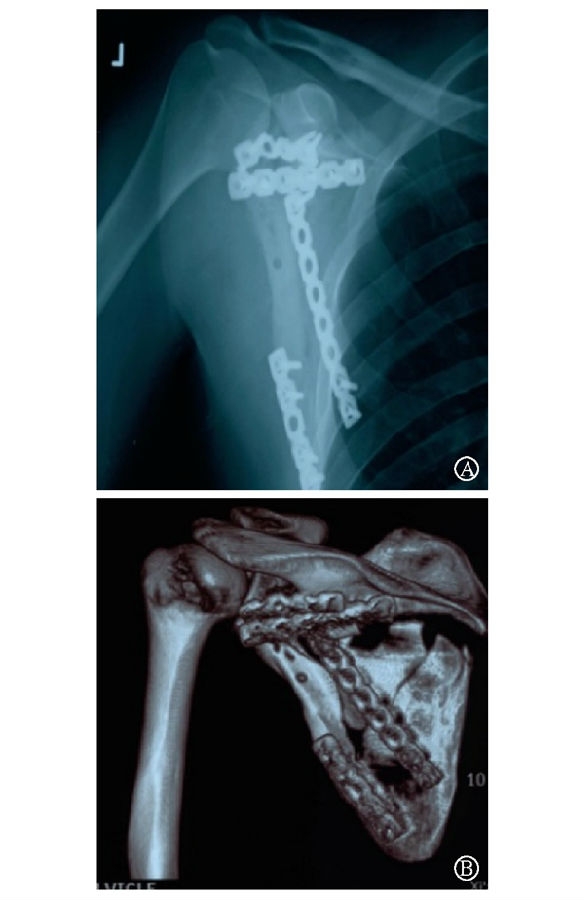

图6 肩胛骨骨折板钉固定

目前,针对此类无法用螺钉固定的肩胛体部骨折,国内许多骨科医师已经做出了另一种选择:缝线固定(图7)。相比板钉固定,缝线捆扎固定也有很大优势,且不可被忽略。

病例1(图8)所示骨折累及肩胛骨体部,单纯使用板钉固定能否更为可靠、便捷?是否还有其他选择?

图8 累及肩胛骨体部的粉碎性骨折

为解决螺钉在肩胛骨体部把持力弱的劣势,在复位骨块后预先在骨折线两侧钻孔,采用两组缝线缝合后以Nice结固定肩胛骨体部(图9)。

术后X线片可见,肩胛骨体部复位良好,因此,配合术后良好的患肢制动,缝线辅助固定技术同样可以稳定维持术中复位(图10)。

图10 采用缝线辅助固定后X线示骨折复位满意,内固定位置良好